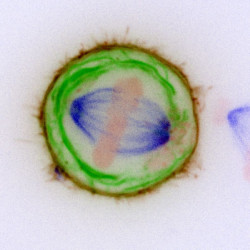

Consiguen trasplantar con éxito un hígado humano tratado durante tres días fuera del cuerpo

Un equipo multidisciplinar de la Universidad de Zúrich (Suiza) ha tratado un hígado humano dañado en una máquina durante tres días fuera del cuerpo y lo ha implantado en un paciente con cáncer. Un año después, el paciente se encuentra bien.